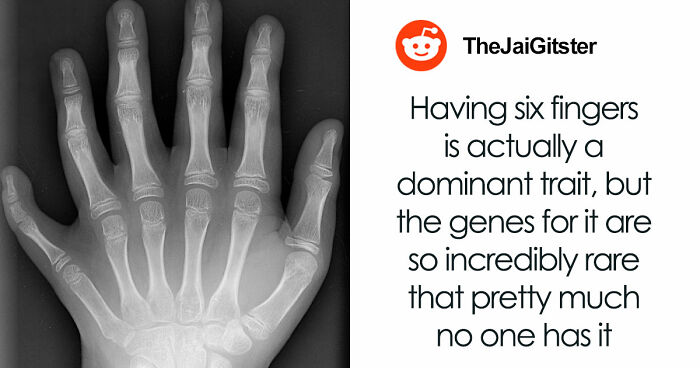

The human body is the best work of art.